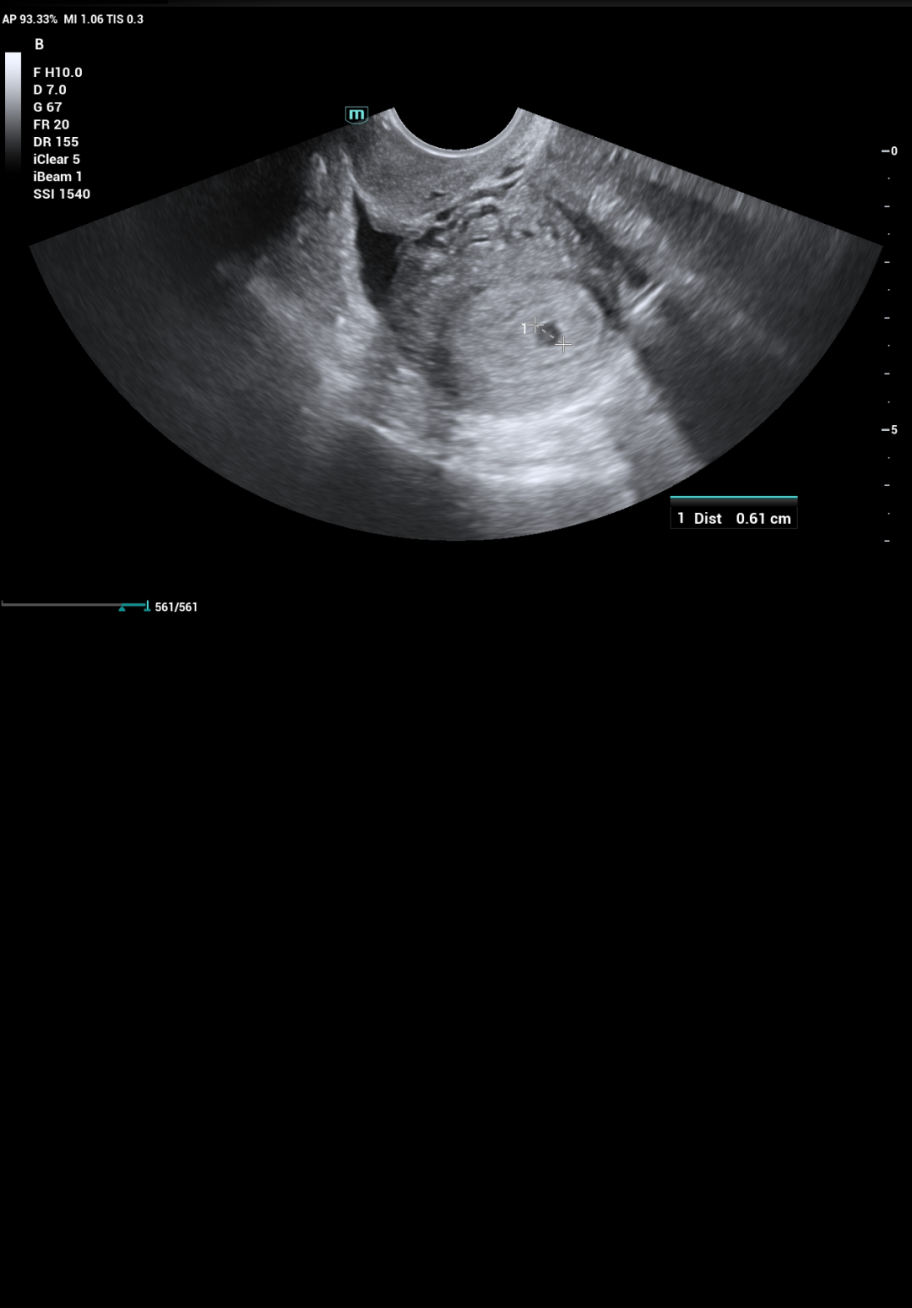

На тази снимка виждате ли сак? АГ не беше много сигурна и малко ме притесни. Трябва да съм в 5гс.

Ами прилича на сакче, раничко е, отидете към 7г.с, тогава ще се види и сакче и ембрионче, и сърдечна дейност дори. Разбира се, ако има бременност.